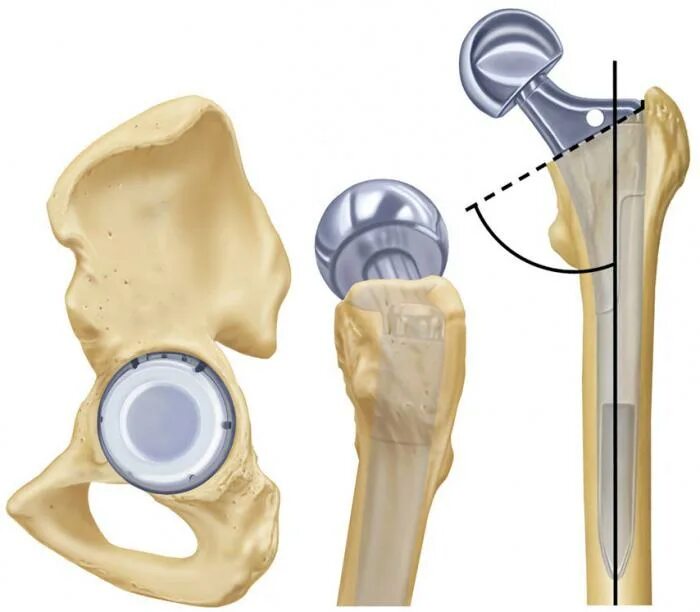

Эндопротез тазобедренного сустава москве